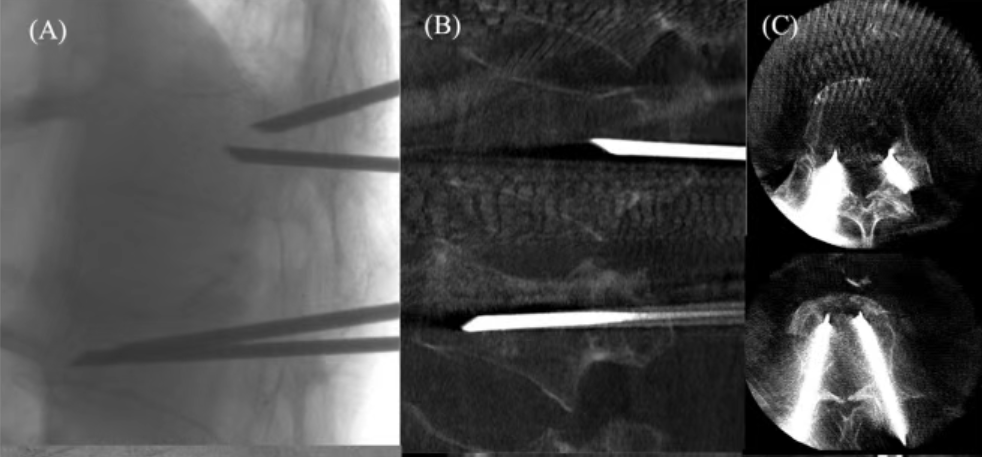

儿童寰枢椎骨化中心千奇百怪,如不了解就会很难区分骨折与正常变异,给临床工作带来困扰。